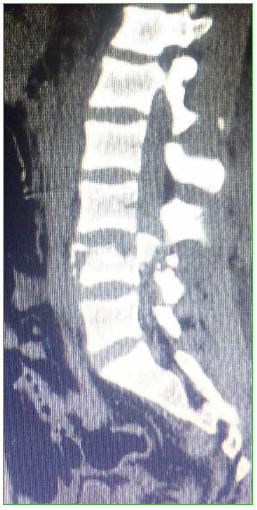

Figura 3.

Caso 1. Tomografía computarizada, corte sagital.

El paciente es trasladado al Servicio de Urgencia del hospital regional y, de allí, es derivado a nuestro centro, a través de su obra social. Ingresa, reactivo, lúcido (escala de Glasgow 15/15), con estabilidad hemodinámica y síndrome de cauda equina incompleto (grado B según el puntaje de la ASIA).19 Se solicitan radiografías y TC de columna cervical, torácica y lumbosacra. Se constata fractura vertebral lumbar baja con compromiso de la cuarta vértebra lumbar (L4), de tipo estallido, con retropulsión de un fragmento voluminoso del muro posterior en el canal, con impronta en el saco dural. La resonancia magnética no mostró una lesión del complejo ligamentario posterior, por lo que se interpreta, según la clasificación AO, como L4: A3, N3, M0 (Figuras 2 y 3). Sin deformidad en cifosis significativa y con un colapso vertebral inferior al 50%. Se constata una lesión hepática asociada, se lo somete a una laparotomía de urgencia y queda internado en la Unidad de Terapia Intensiva.